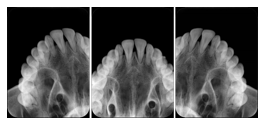

Cephalometric Series Structured Display

Figure OO-2. Cephalometric Series Structured Display

2. A patient requests cosmetic surgery to enhance their facial appearance. The case requires consultation between an orthodontist in New York and an oral surgeon in California. The cephalometric series of 2D projections constructed from the volumetric CT data that is used for the discussion is arranged by a Structured Display for transfer between the two practitioners.